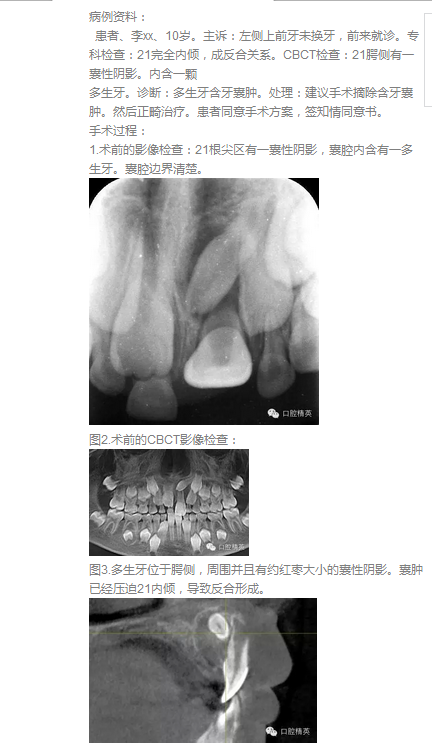

高難度含多生牙囊腫的摘除